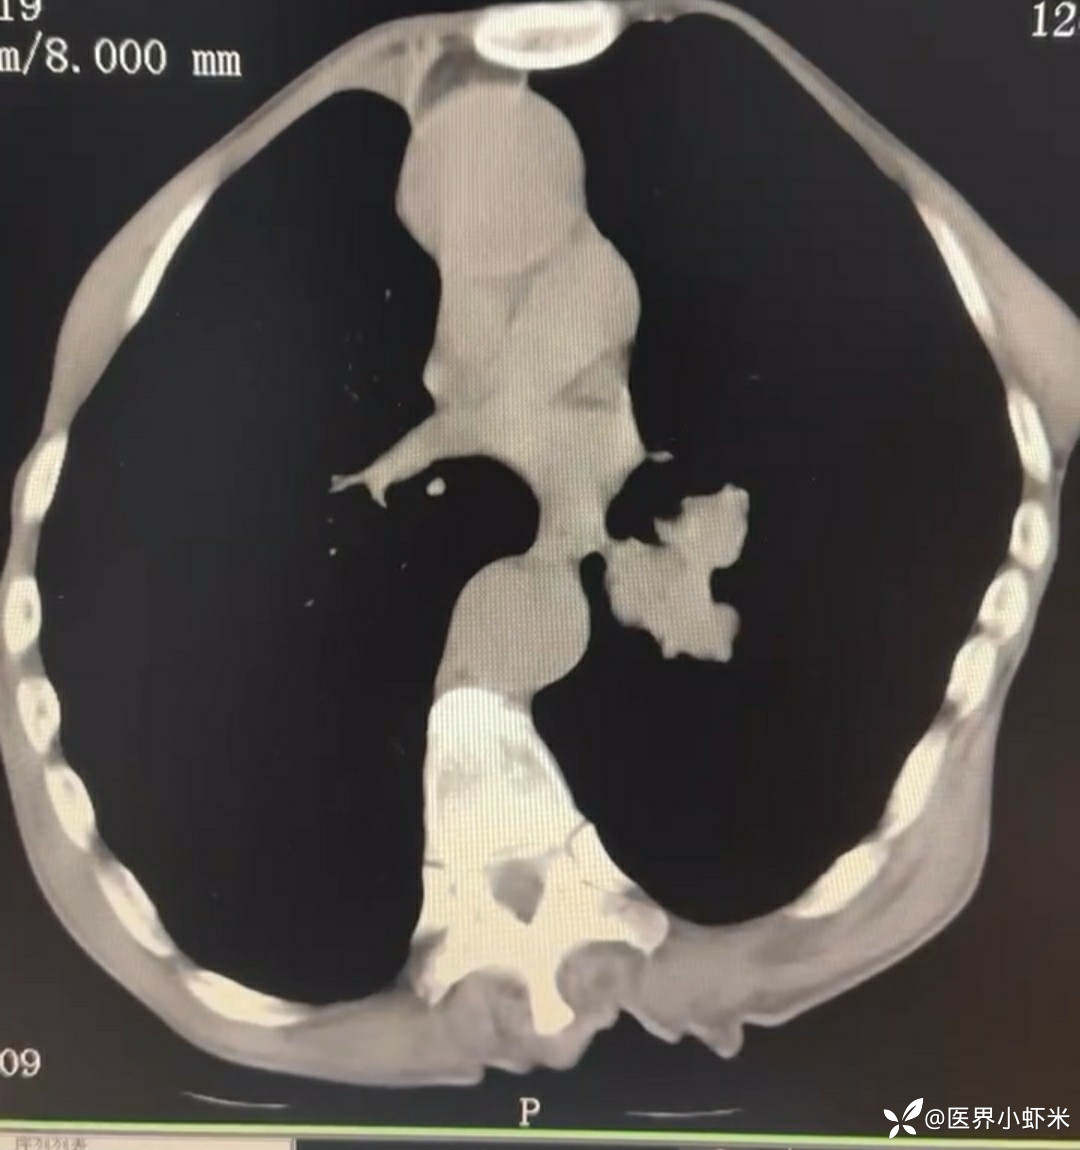

目前考虑:1.中央型肺癌伴2.肝继发恶性肿瘤?2.左丘脑继发恶性肿瘤?3.左丘脑出血?4.肾功能不全5.肝功能异常6右肾萎缩7.肺部感染8.慢性阻塞性肺病7.高血压3级(极高危)。